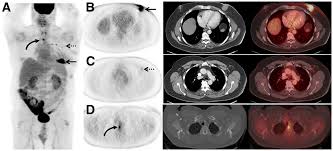

What Cancers Are Detected By Pet Scan - Asymptomatic Myocardial Metastasis From Cancers Of Upper Aero Digestive Tract Detected On Fdg Pet Ct A Series Of 4 Cases Cancer Imaging Full Text : In some instances, depending on the prostate cancer tumor type, fdg pet scans may be used for the restaging of recurrent prostate cancer as well.. Do all cancers show up on pet scan? Once you're ready to start the scan, you'll be asked to lie on your back on a platform. Doctors introduce a tracer into the system and areas with high chemical activity show up on the screen as bright spots. Pet scans can show solid tumors in the brain, prostate, thyroid, lungs, and cervix. To determine whether the cancer has spread to the lymph nodes

Pet scans can be used to: To determine whether the cancer has spread to the lymph nodes There are many different radiotracers used in pet scans that take advantage of other cellular processes. For cancer, pet is especially useful as it can scan the entire body and pinpoint both a primary tumor and areas of metastasis (where the cancer has spread). Prior to a pet scan, the patient receives an injection of a substance that contains a type of sugar attached to a radioactive isotope.

Pet/ct, which is a combination of positron emission tomography (pet) with computerized tomography (ct), is a powerful, essential tool for cancer detection and diagnosis.

The platform will enter a long tube where the pet scan is performed. Pet scans can show solid tumors in the brain, prostate, thyroid, lungs, and cervix. Pet scans can be used to: Positron emission tomography (pet) scans: Your healthcare provider may order a pet scan to check for signs of: The reality is that you cannot rely on a ct scan (or ultrasound, mri, or blood test) to tell you if you have cancer. Positron emission tomography (pet) scan. Doctors introduce a tracer into the system and areas with high chemical activity show up on the screen as bright spots. Pet/ct, which is a combination of positron emission tomography (pet) with computerized tomography (ct), is a powerful, essential tool for cancer detection and diagnosis. Before the scan, you receive an injection of a tracer called radioactive glucose. The scans can also evaluate the occurrence of colorectal, lymphoma, melanoma, and pancreatic tumors. However, as with most studies, there are a few exceptions. It is only with a pet/ct scan that you will know for sure.